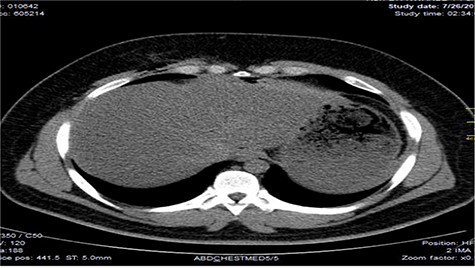

Chest X-ray was normal as shown in Fig. 1. Focused abdominal sonography for trauma (FAST) scan showed mild left perihepatic collection necessitating a thoracoabdominal computerized tomography (CT)-scan which showed external oblique muscle laceration with intermuscular air lucencies and grade 2 hepatic injury as shown in Figs 2–4. Other blood work-up were normal. No other injury was found on secondary survey. His wound was explored under local anaesthesia, primarily repaired, and he was discharged after 24 h of close observation.

Showing lucent air densities tracking through the right intercostal muscles and abutting on the liver in the epigastrum with associated subcapsular haematoma in the left lobe of the liver.